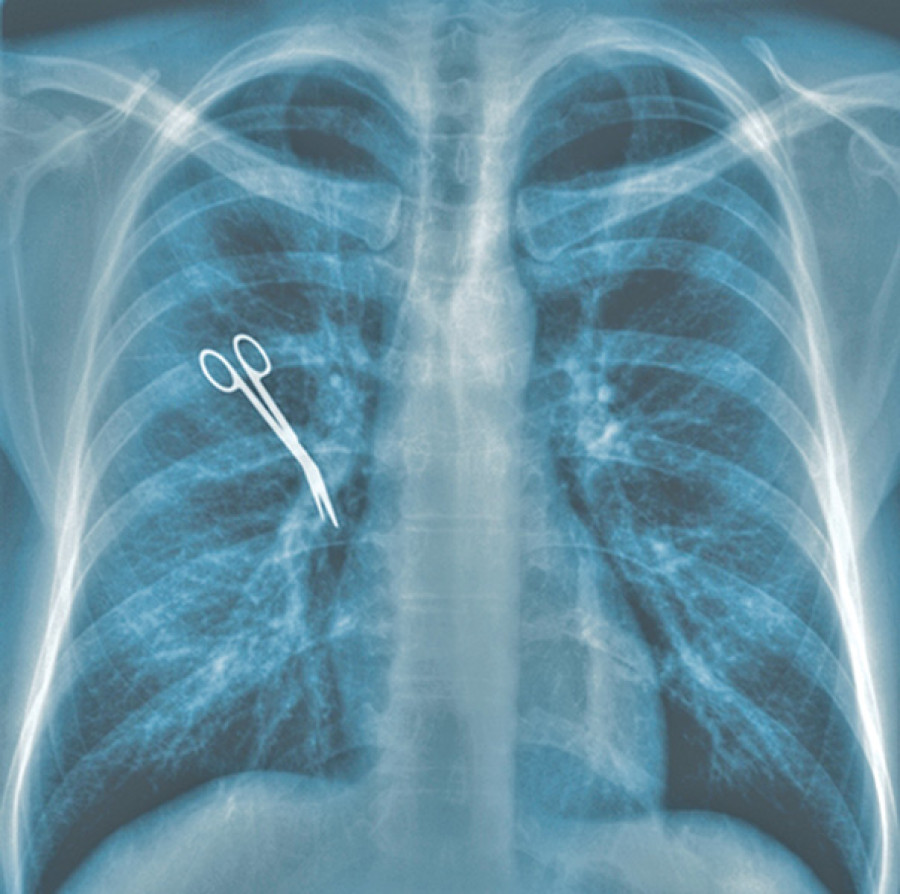

There should be adherence to the Universal Protocol by using the World Health Organisation checklist before, during and after surgery. This not only decreases chances of wrong site, procedure and patient, but also decreases chances of unintentionally leaving foreign bodies and encourages each member of the operating team to be vigilant. Many centres in Nepal have been using the protocol and checklist. However, strict implementation by the administration and legislative bodies cannot be overemphasised. The universal right of patients to have right-patient, right-site and right-procedure should always be the goal of the treating team.